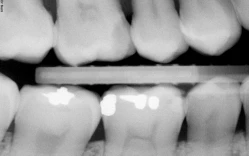

Hình 1: Chu vi chân răng có những điểm lồi lõm nên khi hướng tia X-quang đi qua sẽ tạo hình ảnh thấu quang ở vị trí ranh giới thân – chân.

Hình 2: Các vùng thấu quang cổ răng trên nhiều răng cùng một góc độ chụp và cường độ tia. Chú ý vùng thấu quang ở vị trí nghi vấn dưới mối hàn xoang II Black (hình trái). Chẩn đoán phân biệt bằng triệu chứng và đánh giá độ tụt lợi.